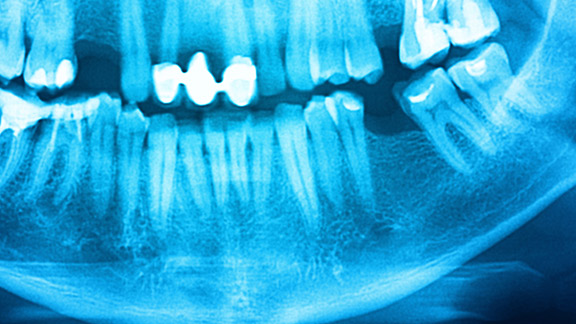

Many patients do not realize that even a single missing tooth can have destructive effects on the jaw. Your jaw bone starts to deteriorate as soon as the tooth root goes missing. Over time, this can cause bite problems, misalignment and changes to the natural contour of the jaw. If you have more significant bone loss, the jaw can look like it is sinking in and your face can even change shape! A bone graft rebuilds that lost tissue to help maintain your natural jaw line.

If you are getting dental implants, you need to have a certain amount of bone available in the jaw for a successful result. Dr. Pack uses Cone Beam x-rays to make sure there is enough bone tissue to support the implant itself and to ensure proper placement of the implant. If there is not enough bone tissue, a bone graft can rebuild that essential bone tissue so there is a firm foundation for dental implants.